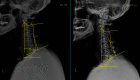

Purpose: To determine the effect of age on sagittal cervical alignment after cervical laminoplasty procedure so as to identify the group with the greatest degree of variation. Study Setting. Single-center retrospective chart review in a tertiary referral hospital. Outcome Measures. The sagittal vertical axis (SVA) (C2-7), T1 slope, and cervical lordosis.

Methods: We included patients who underwent cervical laminoplasty between 2014 and 2018 and divided 60 consecutive patients into two groups using the cut-off age of 65 years. The Paired t-test and Mann-Whitney U test were used to compare changes between preoperative radiographic cervical sagittal parameters and those 1 year after surgery.

Results: Mean patient ages in the older and younger groups were 71 years and 52 years, respectively. The difference of C2-7 SVA was greater in the older group.